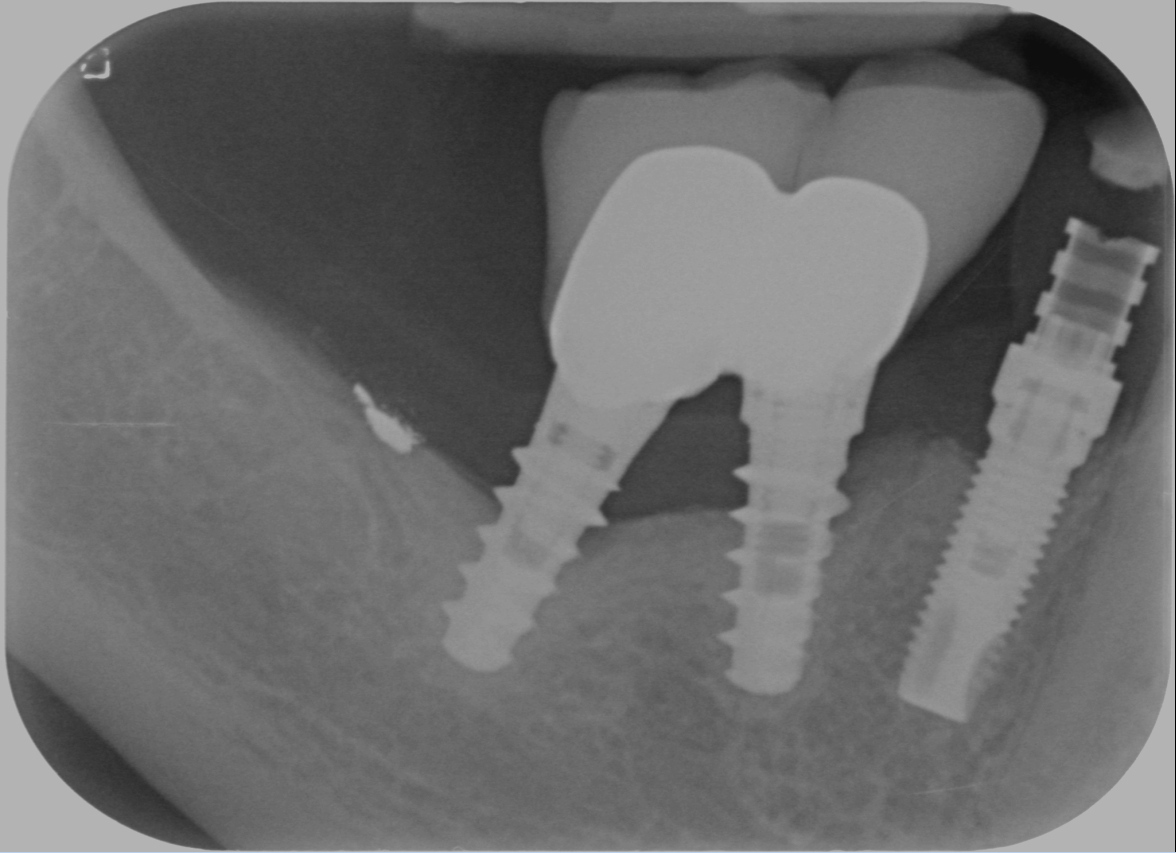

Questo problema si chiama perimplantite. Una vota si mettevano pochi impianti, il tutto veniva fatto in modo molto attento, su pazienti selezionati. Oggi invece gli impianti non si negano a nessuno, li mettono tutti, comprando quelli che costano meno e si fa a gara a chi li fa con il setting meno sterile possibile per dimostrare che si è fighi e funziona lo stesso. Poi sopra ci si mettono le cose più improbabili… guarda qui cosa mi capita di svitare da impianti messi da colleghi pochi mesi fa

Ed ovviamente non si fa alcuna preparazione parodontale perché il paziente ha pochi soldi ed “è già tanto se riesce a pagarmi la vite!”.

Questa è la situazione in cui mi si è presentato il caso:

Dopo la rimozione restavano solo 5 mm prima del nervo. Meno i due di sicurezza fanno 3 e, che io sappia, non ci sono impianti da 3 e anche ci fossero non li userei per trattare un pregresso fallimento!